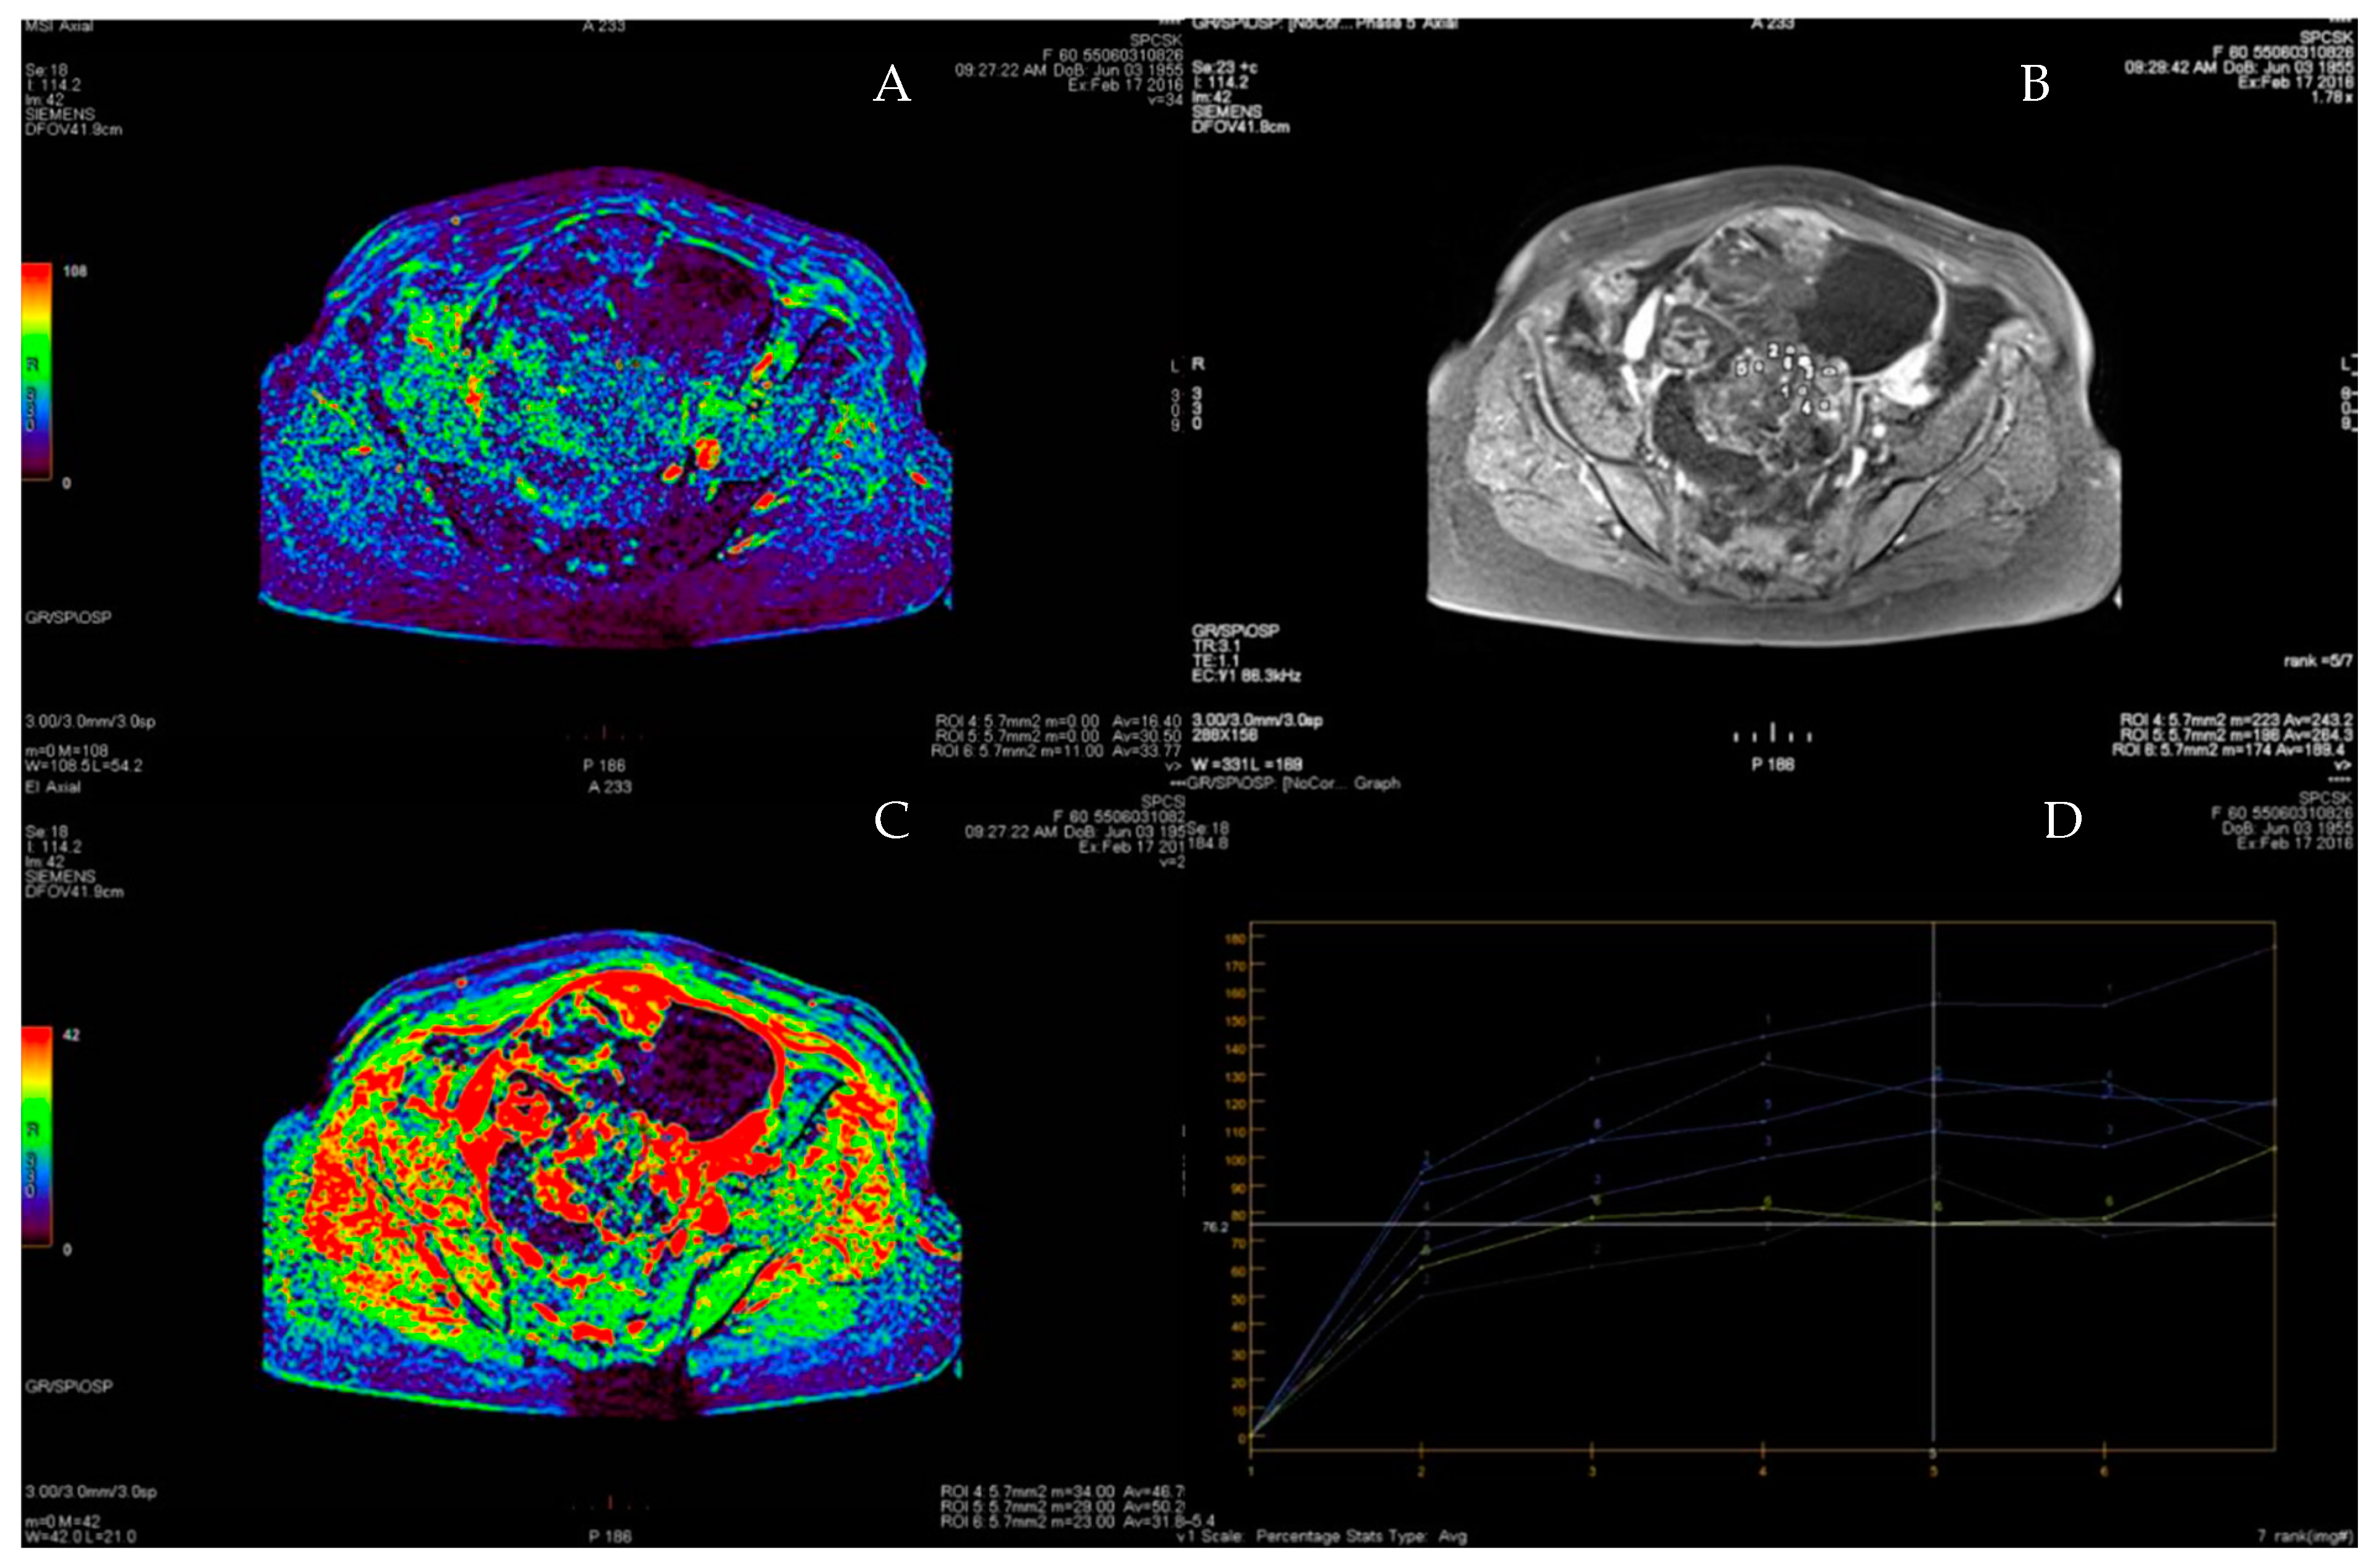

3.1. Primary Tumor DWI

3.3. Primary Tumor DCE

3.4. ROC Curve for LGSC vs. MOC